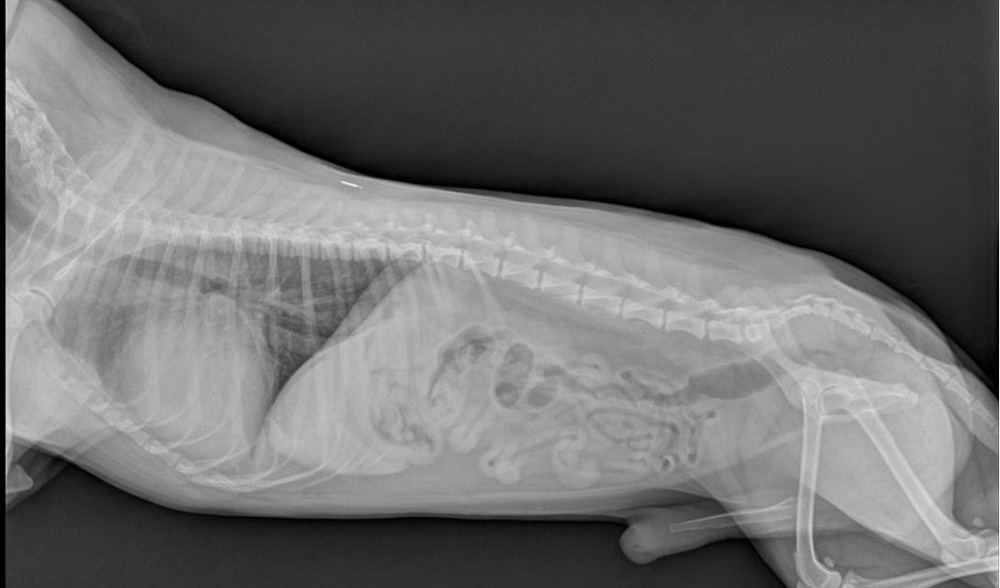

• Chest X-rays to look for heart enlargement and fluid in or around the lungs

These are not “extra for the sake of it”. They help separate primary cardiomyopathy from other causes of thickened walls, and they help stage risk, which is what guides treatment decisions.1, 8